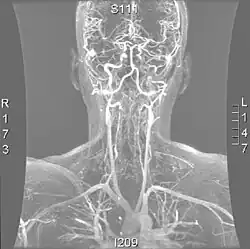

| Arteries of the neck, with arrows indicating the right vertebral artery | |